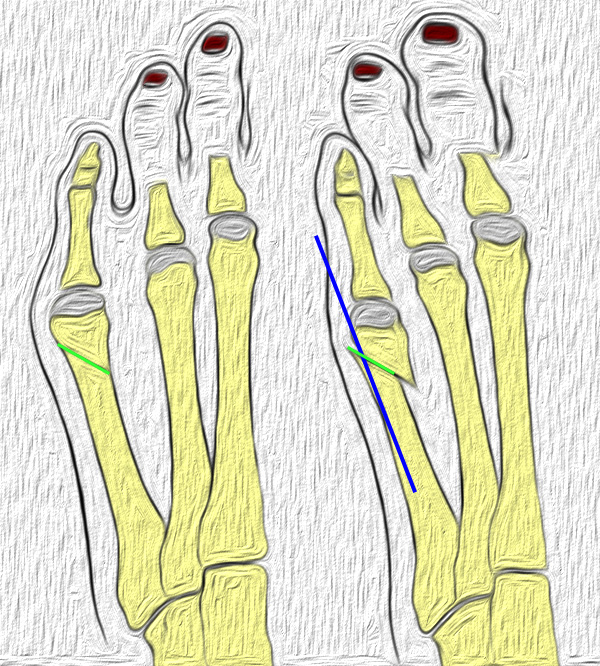

Röntgenmorphologische Einteilung nach Coughlin (I-III) ergänzt durch Fallat (IV) (Arnold 2002) 34

Typ I: Vergrößerter Metatarsale V Kopf

Typ II: Laterale Seitausbiegung des distalen Os metatarsale V

Typ III: Vergrößerter Intermetatarsalwinkel IV/V von mehr als 8°

Typ IV: Kombination von mindestens 2 Typen I-III

Abb. 2: Tailors bunion Typ I bis III (nach Coughlin)